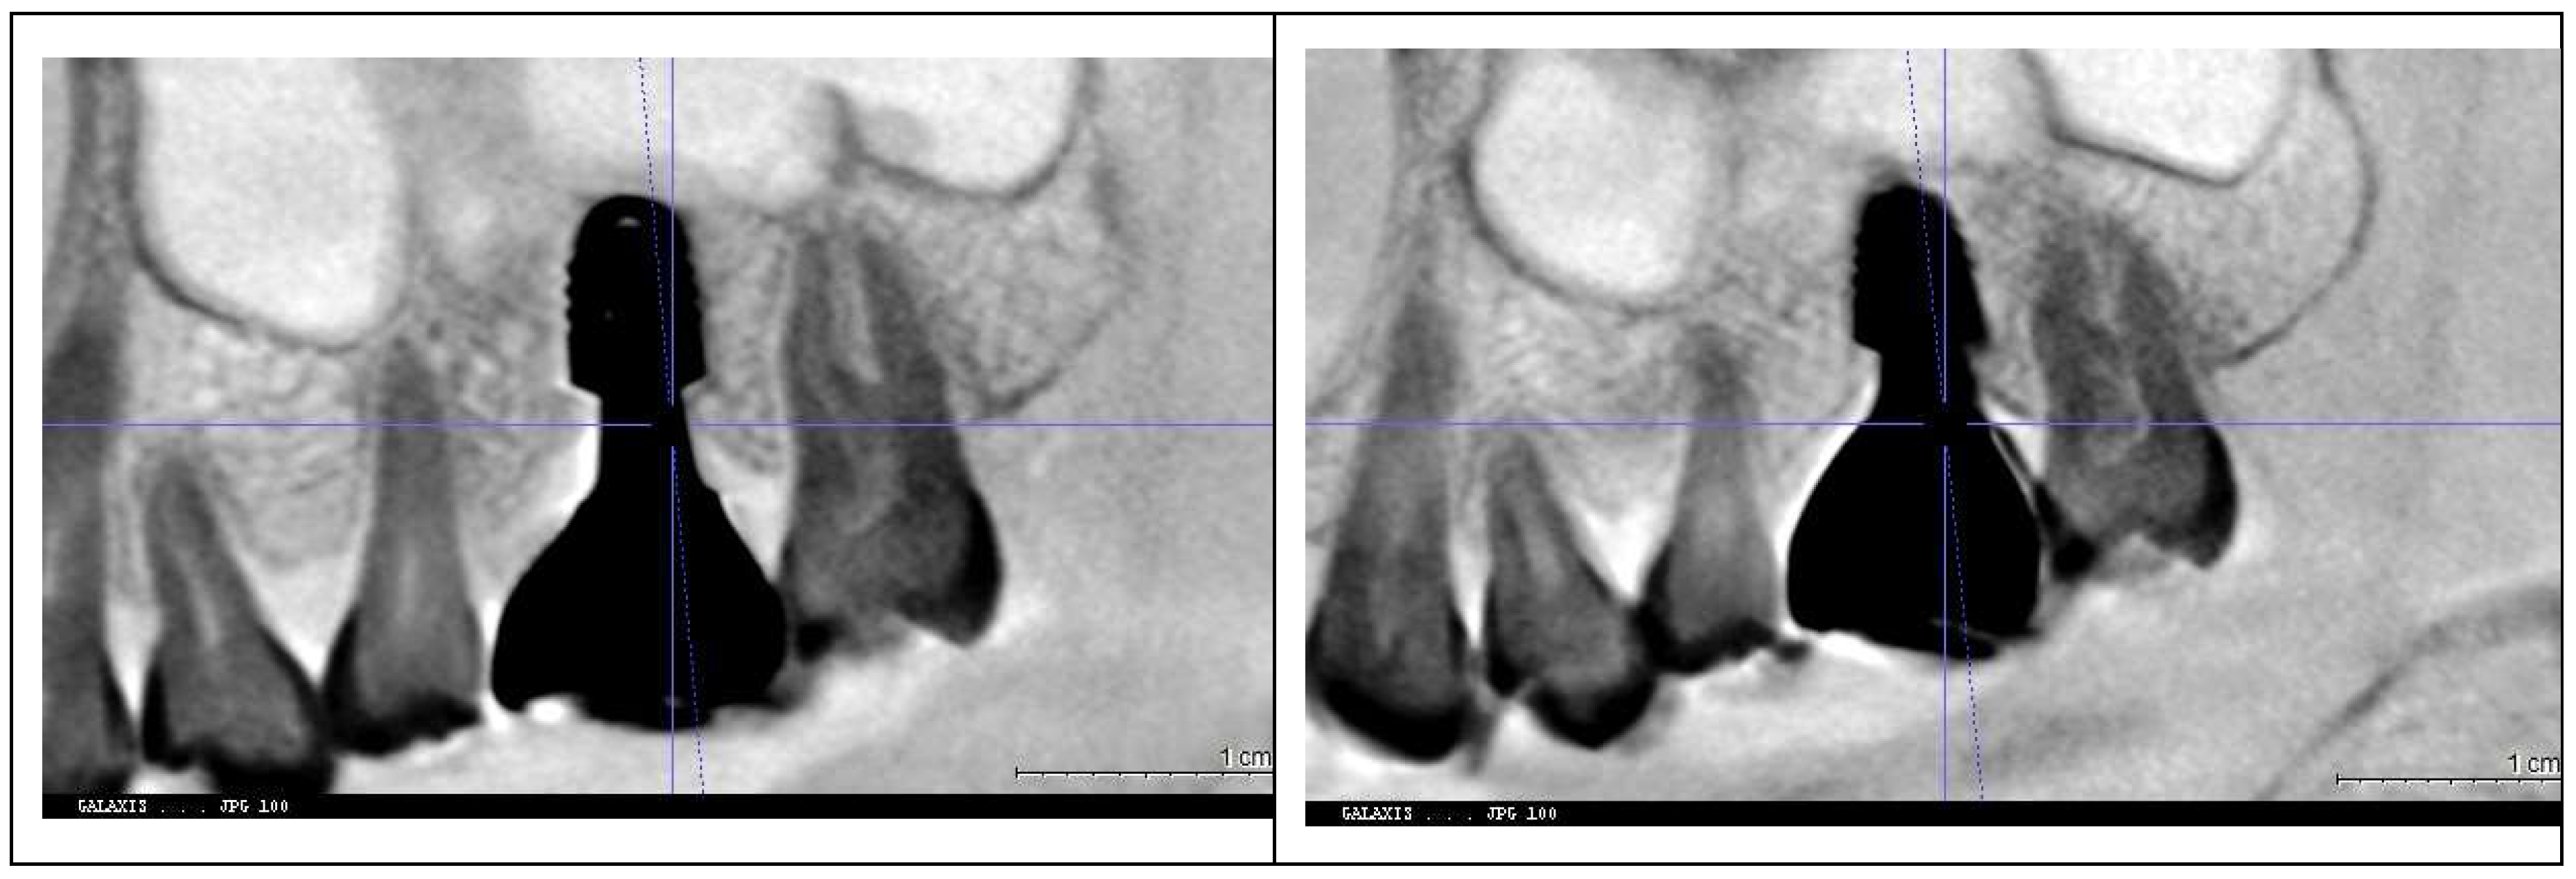

Figure 7 and

Figure 8 illustrate the radiographic changes observed from 2021 to 2024 at the lower right first molar implant site (control site) and the upper left first molar implant site (experimental site), respectively. (

Figure 7,

Figure 7.

This image illustrates the X-ray measurements conducted on the lower right first molar implant, comparing data from 2021 and 2024.

Figure 8.

This image illustrates the X-ray measurements conducted on the upper left first molar implant, comparing data from 2021 and 2024.